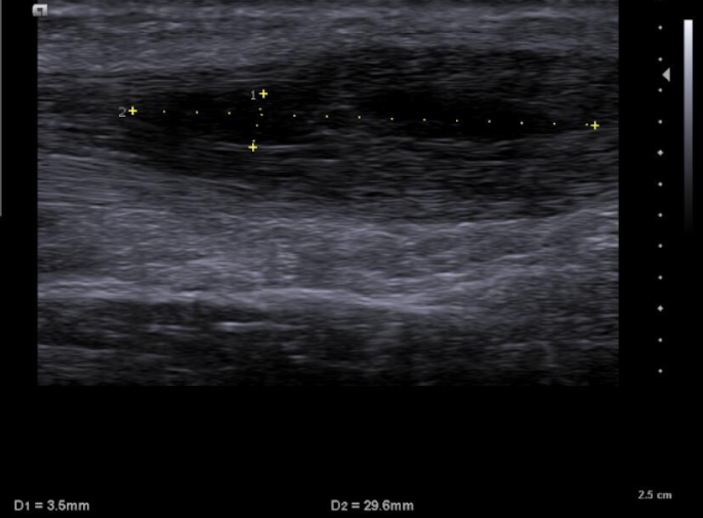

Se emplea sonda lineal L10-5v de forma longitudinal al tendón de aquiles, observando una zona anecoica en interfase del tendón a unos 7 cm de la inserción calcánea, con pérdida de continuidad del patrón fibrilar de las fibras tendinosas y aumento del grosor de este. No aumento de captación en Doppler.